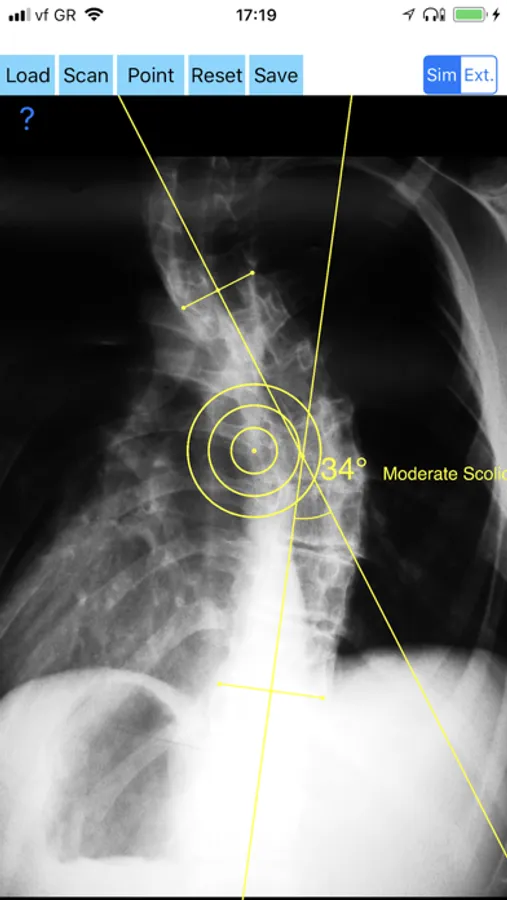

-Offers a very convenient way to determine the most accurate possibly way at once. By marking four points at the same X-ray, at each spine the App calculates the Cobb angle. In cases where values are out of normal ranges, the scoliosis is categorized according to measured angle as mild, moderate, severe. To simplify the process and to minimize inter-observer errors usually by not selecting the actual end vertebra, the app offers also in ext mode the ability to draw the vertical reference line through the patient’s sacrum and to identify more easily the end vertebrae s (ext method).

CobbAngleApp Screenshots